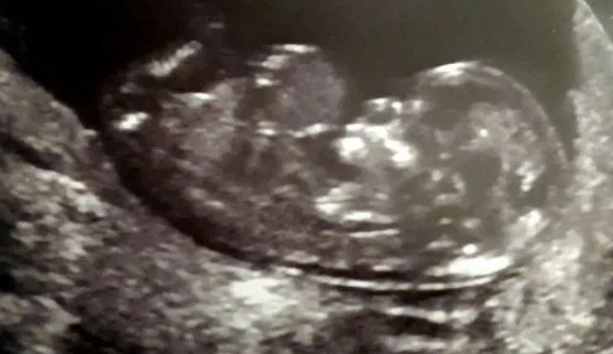

今月9日(現地時間)、英国日刊紙「メトロ」には臓器の一部が体の外に飛び出した状態で生まれた2歳の少女の話を伝えました。英国のケンブリッジに住む、ケリー(30)、ション(34)夫婦とその間に生まれた2歳の娘、ローレルがその主人公です。2017年10月、夫婦は第一子妊娠の知らせを聞き、とても喜びました。2人は10ヵ月間、元気に育てて、無事に生まれることを祈りました。幸せな日々を送りながら過ごして3ヵ月ほど経った頃、夫婦は12週目の超音波検査で、医師から衝撃的な言葉を聞くことになったのでした。赤ちゃんの臓器の一部が、お腹から飛び出しているということだったのです。赤ちゃんはお腹の中にあるはずの臓器が、お腹の外側に突出する「ゼハニア(へそ脱腸胃壁裂球)」という先天的な珍しい疾患を患っていたのでした。

1万人に1人の割合で発生するゼハニアは、腹壁の先天的な欠陥によって肝臓や小腸、大腸など腹腔内の各器官が羊膜と腹膜に包まれ、へその部分で脱腸する疾患です。 通常、妊娠初期の胎児の臓器は臍帯内部で発達した後、数週間後に腹部内部に移動します。 しかし、ローレルの場合、発達過程で腹部の外部に残ったままになってしまったのです。追加的な検査後、医療陣は、「赤ちゃんに脊椎奇形も見られる」とし、「健康に生まれないのはもとより、生き残る可能性は低い」と伝えました。そして、慎重に中絶を勧めたのでした。